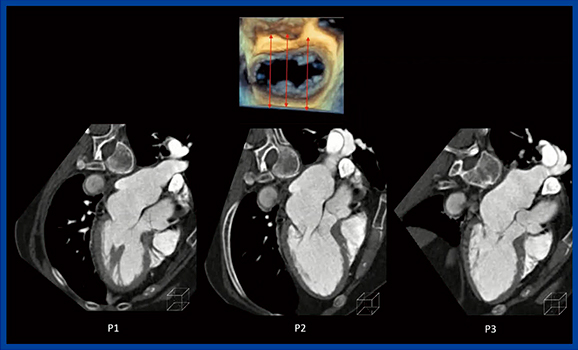

僧帽弁形成術は,患者自身の弁を形成して行う手術で,心エコー検査やCTでの術前評価やプランニングが重要である。CTによるプランニングは,逆流の原因の把握,弁輪の大きさ,弁尖の長さの計測を行う。MPRを用いて,動態を見ながら弁の形態の評価や各種の計測を行っている。原因の把握のために,弁の前後に当たる縦軸に沿って前側壁側から後下壁側に断面を移動させて確認を行う(図4)。これによって,P2で後尖が逸脱していることが確認できた。この症例は,P2が2本の腱索断裂により幅15mmで逸脱していたので,台形切除しZ縫合5針で再建し,人工弁輪を留置して手術が終了した。

図4 MPRによる僧帽弁逆流の原因の評価